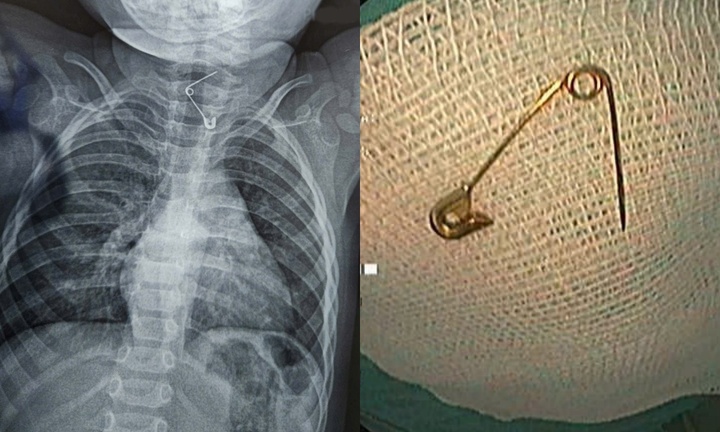

Trước đó, gia đình phát hiện bé đang ngậm một cây kim băng, trong lúc hoảng hốt tìm cách lấy ra đã vô tình đẩy dị vật vào sâu hơn trong họng.